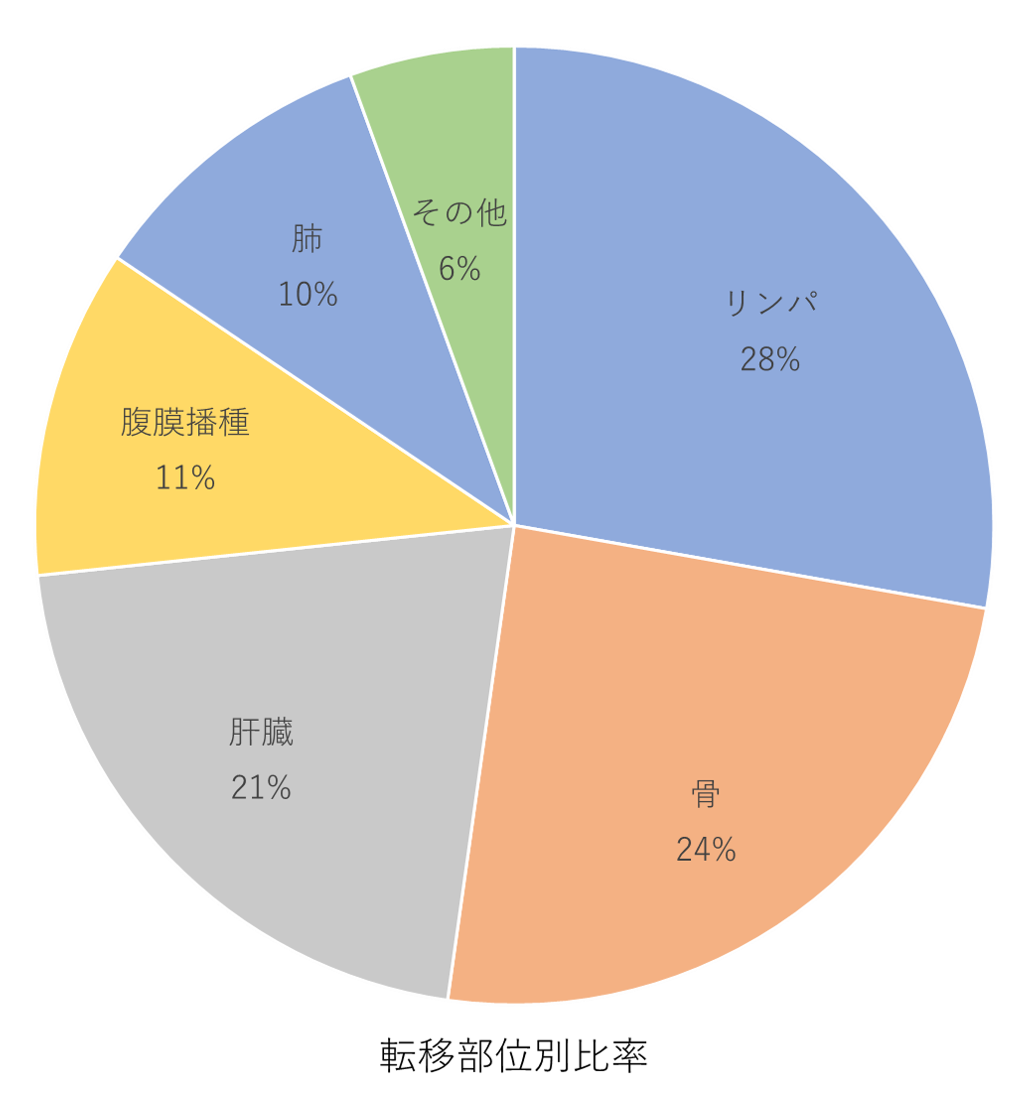

転移部位の傾向は「リンパ」が最も多く28%を占めています。

次に多く転移される部位は「骨」で24%、「肝臓」が21%、「腹膜播種」が11%、「肺」が10%と続きます。

光免疫療法は原発巣だけではなく、転移部位にもご対応できます。